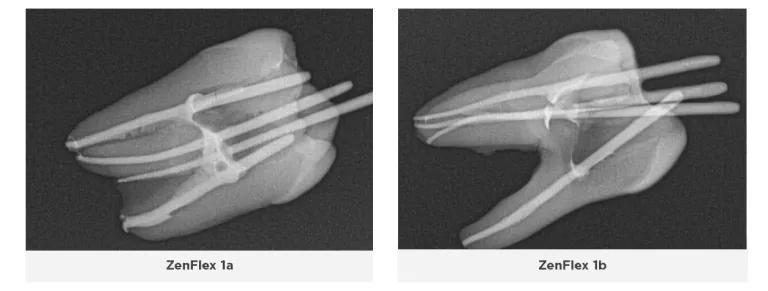

ZenFlex™

ZenFlex files are nickel-titanium files that have undergone a patented heat treatment to provide them with a blend of flexibility and strength not typically seen in a file with this small mass. These files are designed to be as resistant or more resistant to torsional stresses relative to major rotary file competitors despite having a smaller maximum flute diameter and smaller mass. Two unique features that differentiate ZenFlex files from ProTaper Gold and ProTaper Next files are their controlled memory and maximum flute diameter of 1mm.

ZenFlex files undergo a proprietary heat treatment process that improves their strength and resistance to cyclic fatigue, torsional stress and separation, as well as making them significantly more flexible and able to retain their cutting efficiency by preserving their sharp cutting edge. Unlike other manufacturers, Kerr uses a proprietary double heat treatment process. The files are heat treated first, their shape is then ground into them, and then they undergo a second heat treatment to make them stronger and sharper. They also heat treat each file differently based on its mass, therefore the optimum qualities for each file are obtained: smaller more flexible files become stronger, and larger stronger files become more flexible. The files come in both 0.04 and

0.06 tapers, have a non-end cutting tip, and are extremely strong and flexible with controlled memory. Their controlled memory and 1mm maximum flute diameter enable them to follow the natural contour of the canal and be minimally invasive to successfully instrument the canal without removing too much dentin from the coronal and middle thirds and thus preserve the integrity of the tooth structure. ZenFlex files have a centered mass of rotation with a triangular cross-section to provide excellent cutting and debris removal with little to no apical debris extrusion.